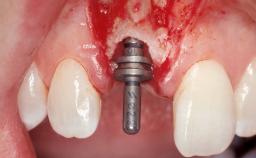

| Placement Protocol | Immediate implant placement |

| Tooth Site | Maxillary incisor or canine |

| Socket Morphology | Single-root socket |

| Socket Integrity | Damage to one or more bone walls |